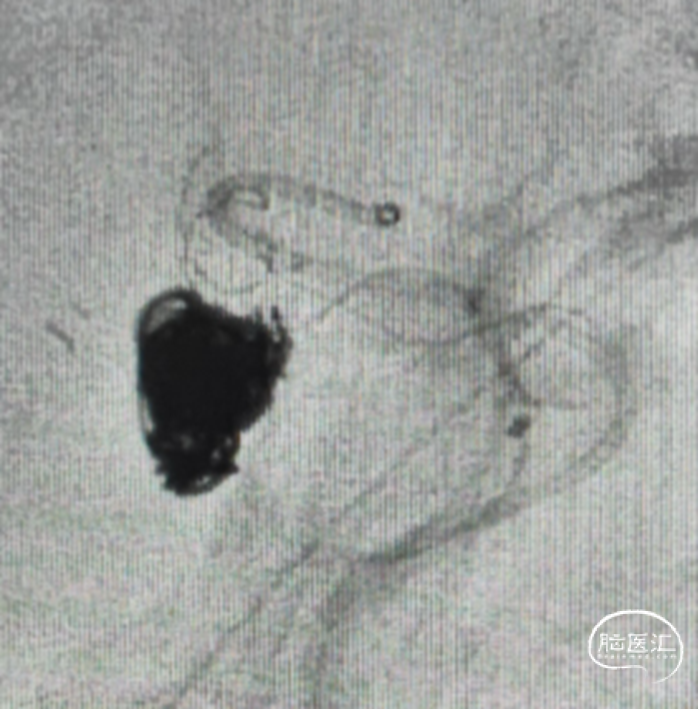

术后第一天CT

术后一周